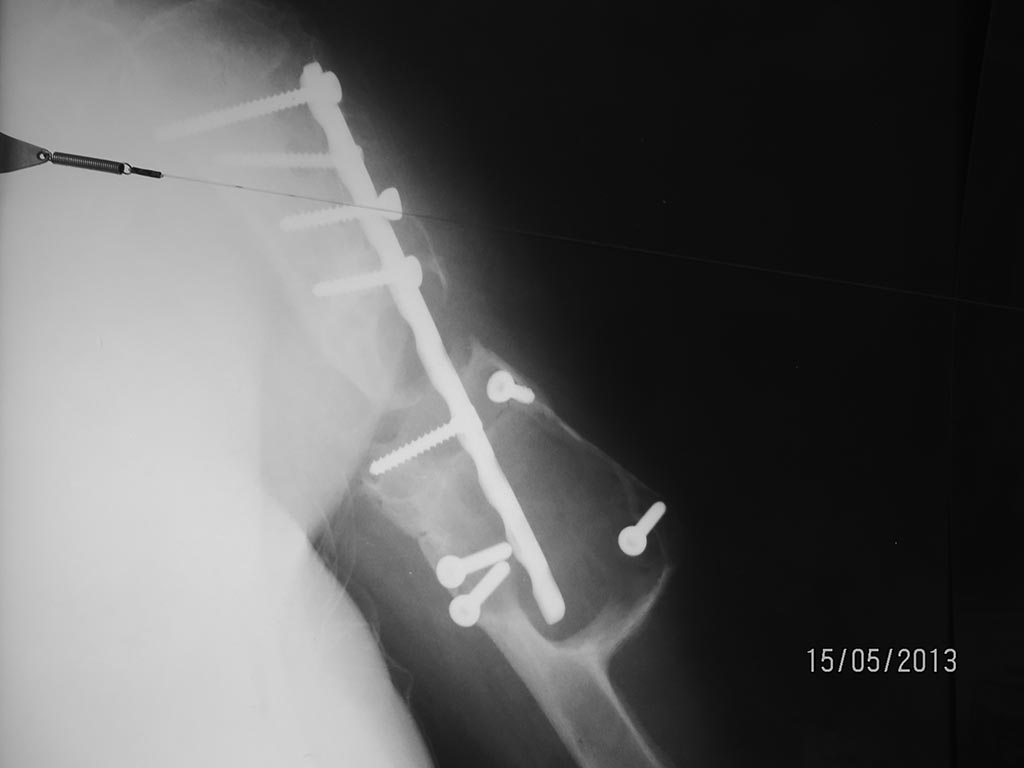

В итоге: выполнить остеосинтез пластиной не реально, винты в склерозированной скорлупе держаться отказывались. Произведена кортикальная костная пластика трансплантатом из малоберцовой кости + гвоздь Богданова и проволочный серкляж. Рентгенограмма мягкая, но видно.